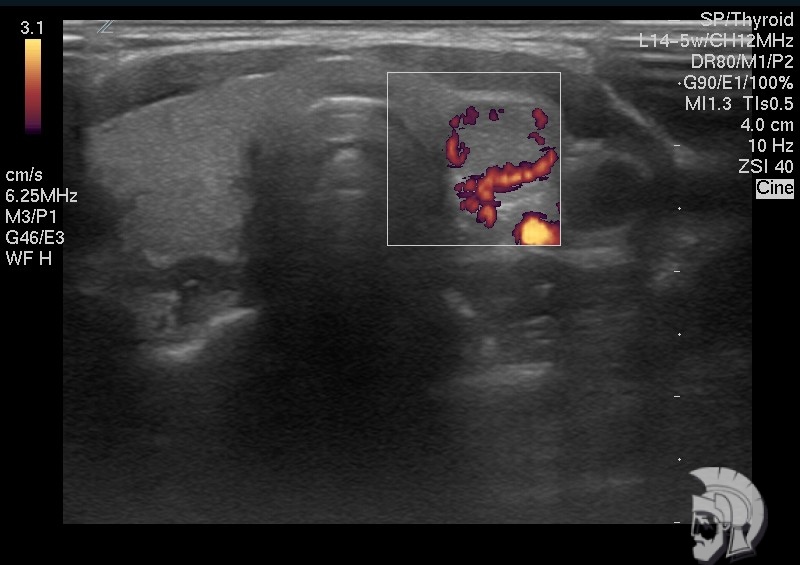

| Фото щитовидной железы. Узел в левой доле щитовидной железы у мужчины 43 лет. При исследовании в режиме энергетического допплера определяется перифокальный (вокруг узла) кровоток |

Обратите внимание на совершенное качество фотографий, свидетельствующих об экспертном классе аппаратов УЗИ!

Использование ультразвуковых аппаратов экспертного класса с режимами энергетического допплера и цветового допплера позволяет врачам Курортной клиники мужского здоровья выявить патологические изменения щитовидной железы на ранних этапах.